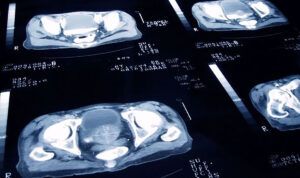

Acest lucru se poate întâmpla în orice vas de sânge. Dar experții spun că anevrismele apar adesea în arterele care alimentează creierul și în părți ale aortei (artera care transportă sângele de la inimă). Anevrismele de acolo sunt grave, în timp ce cele din alte zone, cum ar fi piciorul, pot fi mai puțin periculoase. Cea mai gravă amenințare a unui anevrism este că se va rupe și va provoca un accident vascular cerebral sau o hemoragie masivă, ceea ce poate pune viața în pericol. În plus, anevrismele pot duce la formarea de cheaguri de sânge.

Unul din 50 de oameni are, de fapt, un anevrism cerebral nerezolvat, iar mulți dintre ei nu știu acest lucru. Cele mai multe anevrisme neoplazice sunt asimptomatice și trec neobservate, cu excepția cazului în care au crescut suficient de mult pentru a apăsa pe țesutul cerebral sau pe nervi.